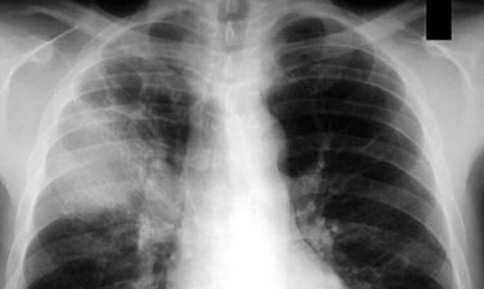

Ô nhiễm không khí luôn được coi là một vấn đề nghiêm trọng và ảnh hưởng rất lớn đến sức khỏe. Đã có nhiều nghiên cứu mối quan hệ giữa ô nhiễm không khí đô thị đặc biệt là ô nhiễm hạt-được tạo ra từ quá trình đốt cháy từ các phương tiên giao thông hoặc các nhà máy với các vấn đề về phổi và tim mạch.

| Nếu tiếp xúc lâu dài với môi trường bị ô nhiễm hạt - những hạt có kích thước nhỏ hơn 10 micron (một sợi tóc của con người có đường kính khoảng 70 micron) sẽ làm tăng nguy cơ bị mắc các bệnh như ung thư phổi, phổi tắt nghẽn mãn tính, khí phế thũng và có thể dẫn đến nguy cơ tử vong. Ngoài ra, nếu tiếp xúc với các chất gây ô nhiễm như Sunful dioxit (SO2), nitơ dioxit (NO2) và ozone (O3) sẽ làm tăng sự phát triển của các bệnh về hen suyễn, viêm phế quản viêm đường hô hấp,… |

Ngoài việc gây tổn thương phổi, ô nhiễm không khí còn là một mối đe dọa đối với sức khỏe của tim mạch. Theo báo cáo vào đầu những năm 2000 của Tạp chí Hiệp hội Y khoa Mỹ (JAMA), các nhà nghiên cứu đã làm cuộc nghiên cứu kiểm tra sức khỏe lâu dài trên 500.000 cá nhân và thấy rằng, khi ô nhiễm không khí tăng, ngoài những ca tử vong do hen suyễn, viêm phổi, … còn có sự gia tăng đáng kể của các ca tử vong liên quan đến đau tim và đột quỵ. Các nhà nghiên cứu giải thích rằng: ô nhiễm không khí làm tăng Stress oxi hóa, gây ra các chứng viêm ở phổi làm cho cơ thể sản sinh ra các chất làm giảm chức năng tim và huyết áp và là nguyên nhân làm gia tăng tử vong do tim mạch.